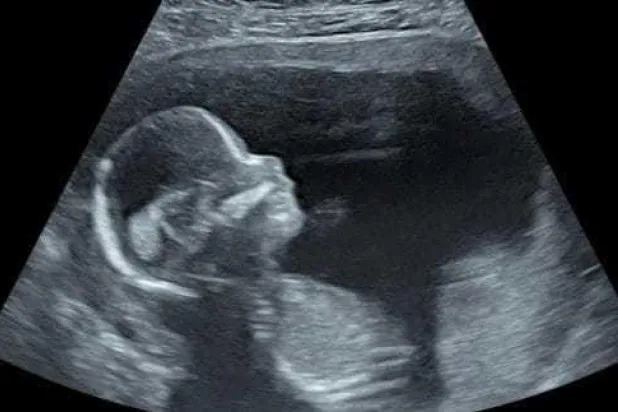

قد يتعرض الجنين لمشكلات تكوينية خلال فترة نموه داخل رحم أمه، وهذا ما أوجب على المرأة الحامل المتابعة المنتظمة في عيادة النساء والتوليد منذ لحظة اكتشاف الحمل، وذلك للكشف المبكر عن أي عيوب خلقية تكوينية لدى الجنين، لاتخاذ القرار باستكمال الحمل أو إنهائه.